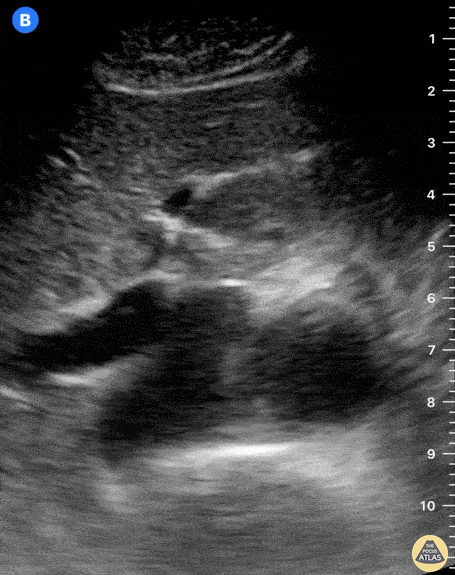

The two round, anechoic structures laying on top of a hyperechoic vertebra are the IVC to the left of the screen (patient’s right), and the thicker, contractile aorta to the right (patient’s left). Deep inspiration or a sniff test demonstrates a collapsible IVC in normal subjects. Consider, however, that visualization of both these vessels may certainly be obscured by very obese patients or those with subcutaneous emphysema, significant bowel gas, ascites, or a large ventral hernia. This clip is taken over the subxiphoid region, transverse to the body’s axis, and with the probe marker oriented to the patient’s right. Dr. Felipe Urriola P., Emergency Unit, Puerto Aysen Hospital, Chilean Patagonia.